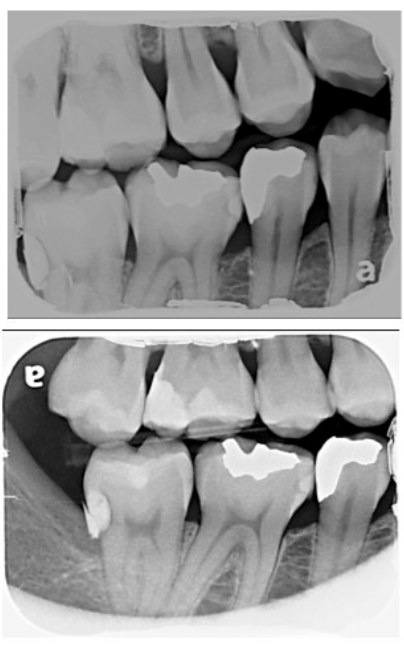

3일전 치과검진 다녀왔고 방사선상 아래턱 두번째 어금니에 인접면 (오른쪽) 충치소견을 받았습니다.

• 1번 째 사진

사진으로 봤을 경우에는 오른쪽 아래 맨 뒤에 치아 뒤쪽에 있는 충전 물이 부분적으로 탈락한 것으로 보입니다.

해당 부위는 잇몸 안쪽에 있는 부분이기 때문에 접근이 매우 어려워서 치료하기가 까다로운 부위인데이 부분에 충전 물이 탈락이 되거나 부착된 부위도 떨어졌다면 외부 자극에 민감할 수 있습니다.

해당 부위를 너무 강하게 자극하지 마시고 한국에 오실 수 있으면 치과에서 진료를 받아 보는 것이 좋습니다.